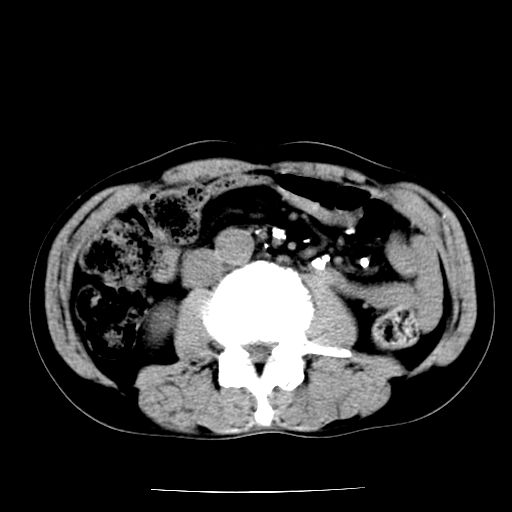

男,59岁,“结核性胸膜炎”30余年,胸部经常疼痛,多次x检查提示“肺部”炎症。腹部疼痛5日,b超提示:“肝内短管结石,余显示不清,建议进一步检查。”

两肺结核并右侧胸腔积液;脾脏、腹腔及腹膜后淋巴结结核[陈旧性];肝内胆管结石

胸部腹部都是结核(双肺。纵隔淋巴结,肝脏,脾脏,肠系膜)

两肺结核并右侧胸腔积液;脾脏、腹腔及腹膜后淋巴结结核[陈旧性];肝内胆管结石。直肠息肉?